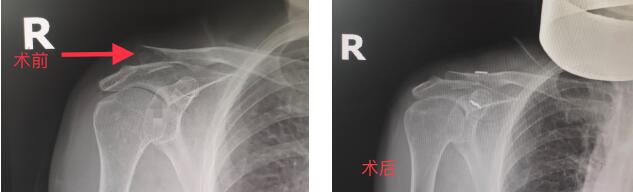

羅江區(qū)人民醫(yī)院成功開(kāi)展首例調(diào)節(jié)型帶袢鋼板手術(shù)

? ? ? ?近日,羅江區(qū)人民醫(yī)院骨科成功開(kāi)展首例調(diào)節(jié)型帶袢鋼板(Endobutton)手術(shù),此項(xiàng)新技術(shù)的開(kāi)展,標(biāo)志著骨科在鎖骨肩峰端骨折治療領(lǐng)域更上一個(gè)臺(tái)階。

? ? ? ?3月30日,羅江區(qū)人民醫(yī)院骨科為曾大娘進(jìn)行了右鎖骨肩峰端骨折,調(diào)節(jié)型帶袢鋼板(Endobutton)植入,微創(chuàng)下骨折復(fù)位固定手術(shù),術(shù)中C臂透視見(jiàn)鎖骨肩峰骨折對(duì)位好,鋼板位置佳,手術(shù)達(dá)到預(yù)期效果。術(shù)后第二天,曾大娘就能進(jìn)行患肢功能鍛煉,自我感覺(jué)好,未訴疼痛,術(shù)后第三天出院。

? ? ? ?調(diào)節(jié)型帶袢鋼板(Endobutton)技術(shù),是一種比較新穎的微創(chuàng)手術(shù)方式,可應(yīng)用于鎖骨肩峰端骨折、肩鎖關(guān)節(jié)脫位、急慢性關(guān)節(jié)周圍韌帶損傷等疾病。與傳統(tǒng)手術(shù)相比,該手術(shù)創(chuàng)傷小,出血量少,可明顯減少術(shù)后疼痛,縮短關(guān)節(jié)恢復(fù)時(shí)間,改善關(guān)節(jié)的活動(dòng)度,且不需要拆除內(nèi)固定,免除了患者二次手術(shù)的痛苦。